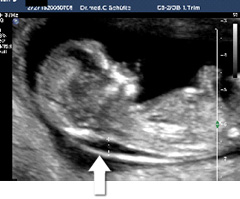

Messung der Nackentransparenz

Das zweite Bild zeigt eine auffällige

Nackentransparenz.